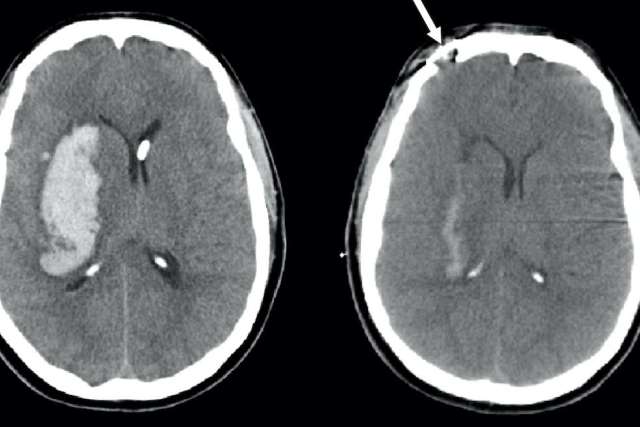

A person who is having a stroke may temporarily lose the ability to speak, walk or move their arms. For many stroke survivors, however, some of these lost abilities return spontaneously during the first few weeks after the stroke. Few patients recover fully and most are left with some disability, but the majority exhibit some degree of spontaneous recovery.

Doctors and scientists don’t fully understand how this happens, because the brain does not grow new cells to replace the ones damaged by the stroke. Neurologists have generally assumed that the brain instead recruits existing neurons to take over for those that are lost.

A stroke occurs when the blood supply to a certain part of the brain is interrupted, such as by a blood clot. Brain cells in that area become damaged and can no longer function. Depending on which part of the brain has been damaged, the skills lost after the stroke may include motor skills, speech or sensory perception.